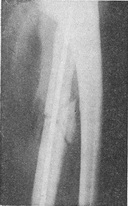

![]() Рис. 11. Осколковий перелом діафіза променевої кістки (стан після операції) |

У зв'язку з тим, що часто буває неможливо к репонувати відламки, а ще важче утримати їх у правильному положенні за допомогою гіпсової пов'язки, показано оперативне лікування, при якому застосовуються різні фіксуючі конструкції: металеві штифти, компресійні пластинки, шурупи, спиці. Широко використовуються кісткова ауто - і гомопластика, декортикація (рис. 11).